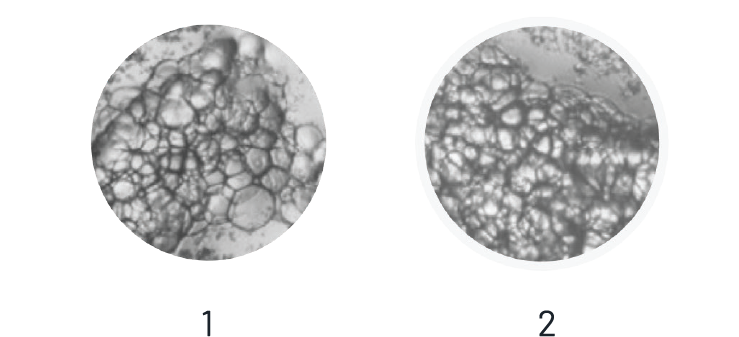

The EXAFAT samples (Fig. 1 & 2) exhibits a uniform composition, free from oil and red blood cells (RBCs).

In contrast, the images of the lipoaspirate obtained using the Coleman technique (Fig. 3 & 4) show blurred sections, indicating RBCs.